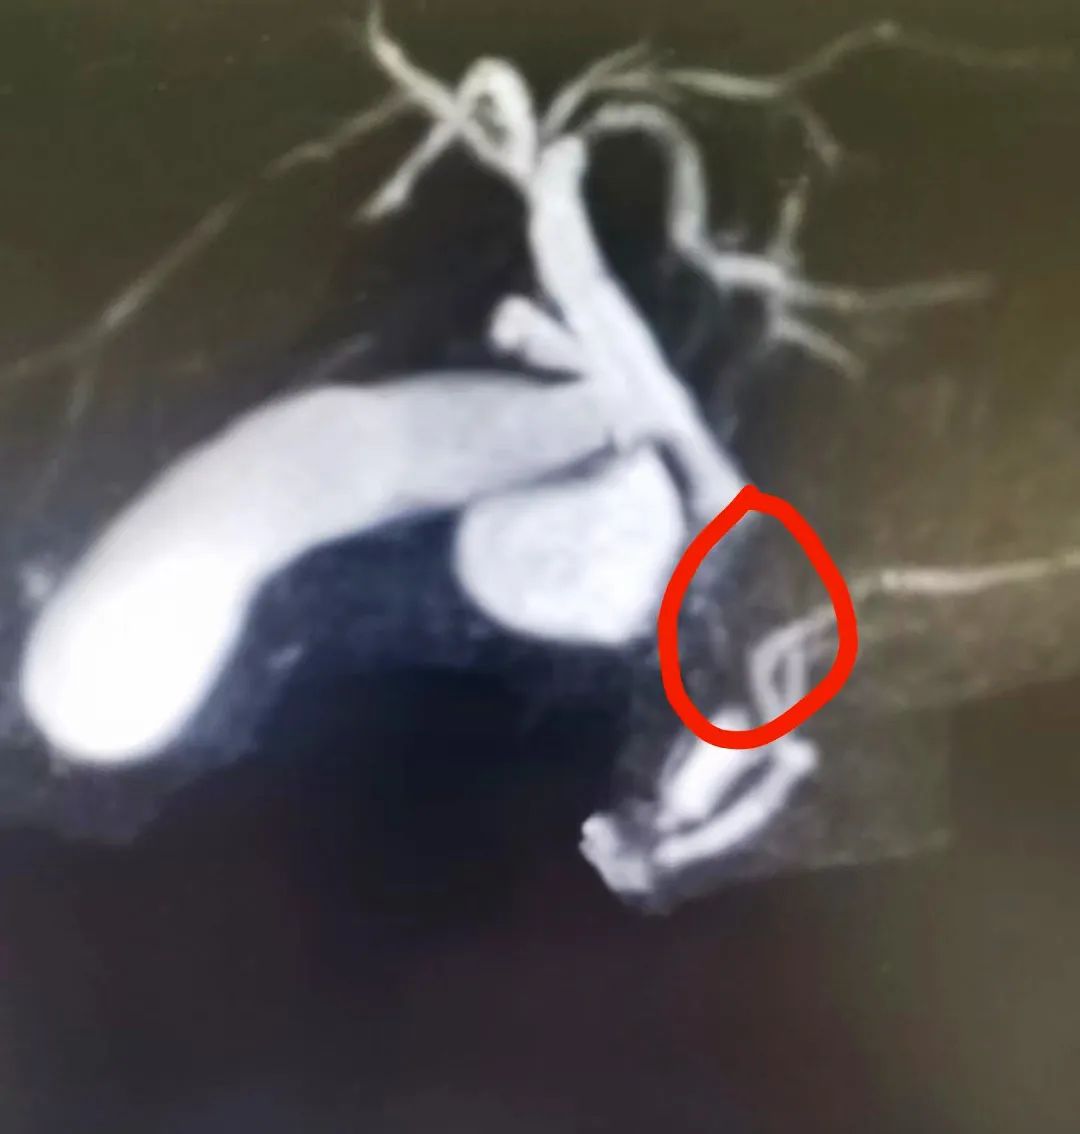

經(jīng)腹部彩超、核磁共振等檢查

醫(yī)生很快幫郝先生揪出“元兇”

急性化膿性膽囊炎

伴膽囊結(jié)石

膽總管末端結(jié)石

伴膽總管擴(kuò)張

膽道鏡進(jìn)入膽總管

完整取出約1*5cm結(jié)石

形似成年人小拇指大小